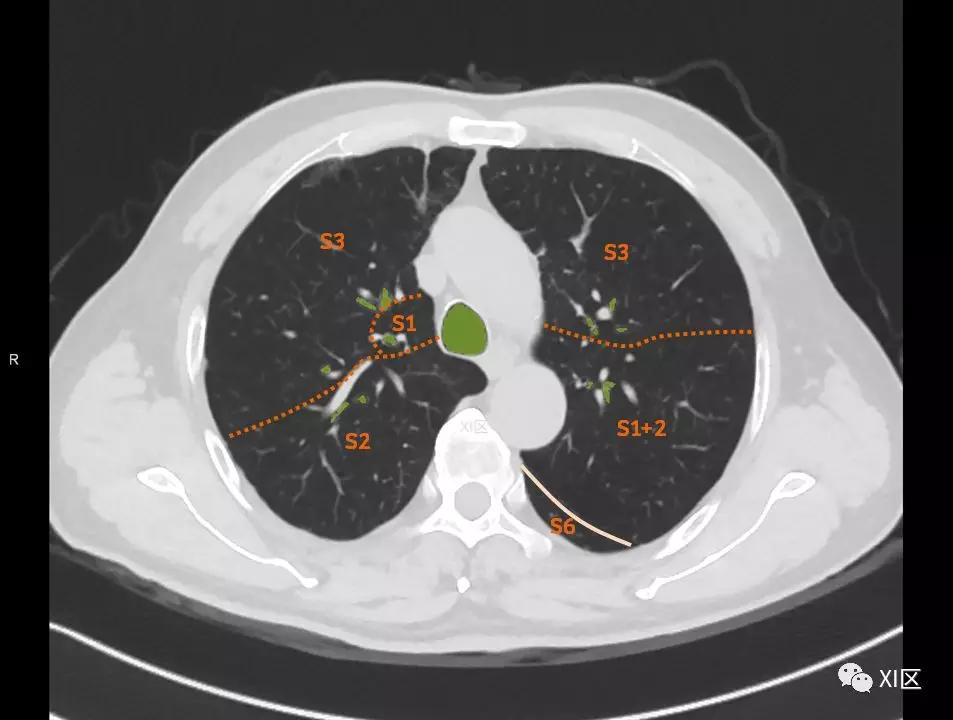

肺的断层分段示意图

在进行肺的分段时,可以上下观察浏览,沿着相应气管的走形可以更容易准确地进行分段。